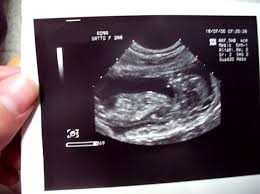

L’indagine ecografica costituisce infatti il metodo di imaging medica più diffuso e utilizzato durante la gravidanza; in particolare, il suo uso in epoche precoci di gestazione trova una maggiore applicazione nei casi in cui sia richiesta una procedura di concepimento assistito, oppure nei casi in cui si ha ragione di temere un aborto spontaneo.

È il prestigioso Royal College of Obstetricians and Gynaecologists a rendere noti i risultati di una recente ricerca scientifica, secondo la quale l’uso degli ultrasuoni nelle prime 10 settimane di gravidanza (epoca oltre la quale l’“embrione” viene considerato “feto”) dovrebbe essere applicato solo quando clinicamente necessario.

In letteratura scientifica non esistono prove circa l’effetto cumulativo dell’esposizione ripetuta agli ultrasuoni, tuttavia nelle prime 10 settimane di gestazione l’embrione è in una condizione di spiccata sensibilità e vulnerabilità sia per le sue dimensioni, sia per il processo di divisione cellulare che è estremamente più rapido in questa fase rispetto ai periodi successivi; sembrerebbe inoltre che sia maggiormente sensibile allo stress termico.

In particolare, il rilievo nel mirino dell’analisi degli studiosi sono le ecografie in 3D e 4D, il cui ricorso è sempre più diffuso e spesso esplicitamente richiesto dalle future madri allo scopo di conservare immagini di qualità superiore come ricordo: queste tecnologie comportano tempi di scansione più lunghi e sono associate a potenze superiori, con conseguenti maggiori rischi per l’embrione.